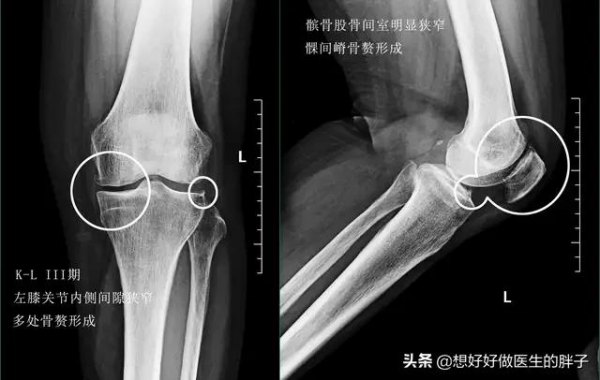

通常情况下,我们根据膝关节x线的表现中关节间隙是否狭窄,以及骨赘形成的程度将骨关节炎分为4期。

三期的骨关节炎患者往往因为软骨的磨损,关节间隙已经开始出现了明显的狭窄,骨赘量也相应有明显的加大。